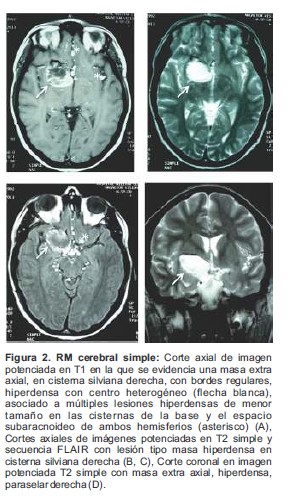

Paciente femenino de 21 años de edad, que acude a la consulta de neurocirugía con clínica de cefalea de 10 años de evolución, asociada a eventos de sincope en los últimos 2 años, los cuales se precedían de sensación de vértigo y parestesias generalizadas. Al interrogatorio no reveló antecedentes de importancia, el examen físico general y neurológico no evidenció anormalidad alguna. La evaluación con tomografía craneal (TC) simple presenta una lesión con densidad de grasa (hipodensa) en la cisterna silviana derecha asociada a otra lesión cálcica adyacente anterior (Figura 1). Se realiza resonancia magnética (RM) cerebral simple y contrastada evidenciándose en las imágenes simples, una masa hiperdensa extra axial, en cisterna silviana derecha, con bordes regulares, de aproximadamente 3.2x2.1cm de diámetro, asociado a pequeñas lesiones hiperintensas diseminadas en las cisternas de la base (Figura 2), en la imagen contrastada de T1 se ve una masa hipointensa que no capta el medio de contraste (Figura 3). Por los hallazgos imaginológicos descritos se consideró que se trataba de un quiste dermoide roto y se procedió a preparar la paciente para el manejo quirúrgico de la lesión. Se realiza craneotomía fronto-temporal derecha, bajo visión microscópica se procede a disecar el valle de Silvio, hasta encontrar la lesión tipo masa, capsular, de color amarillento, con grumos grasos a su alrededor y vellosidades en su interior, extra axial, creciendo en la base craneana media, adherida al nervio óptico derecho y la arteria carótida interna derecha, se procede a realiza escisión completa de la lesión incluyendo la cápsula. Se realiza TC simple en el posoperatorio temprano en la cual se confirma la resección completa de la lesión (Figura 4). El informe de patología posteriormente confirmaría el diagnóstico de quiste dermoide. El egreso hospitalario se dio 3 días después del procedimiento quirúrgico sin complicaciones.

Figura 2. RM cerebral simple: Corte axial de imagen potenciada en T1 en la que se evidencia una masa extra axial, en cisterna silviana derecha, con bordes regulares, hiperdensa con centro heterogéneo (flecha blanca), asociado a múltiples lesiones hiperdensas de menor tamaño en las cisternas de la base y el espacio subaracnoideo de ambos hemisferios (asterisco) (A), Cortes axiales de imágenes potenciadas en T2 simple y secuencia FLAIR con lesión tipo masa hiperdensa en cisterna silviana derecha (B, C), Corte coronal en imagen potenciada T2 simple con masa extra axial, hiperdensa, paraselar derecha (D).